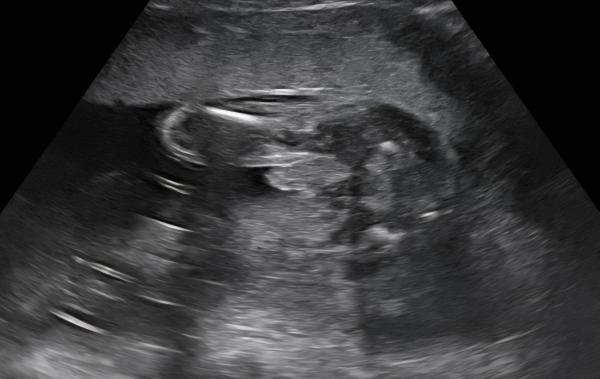

Hallo Ich bin schwanger und wir wollten gerne das Geschlecht unseres Babys erfahren. Im Ultraschall bei Woche 18+3 hat sich das Baby gezeigt, siehe Ultraschallbild (Potty Shot). Für uns sah das ziemlich eindeutig nach Junge aus🩵😊 Jedoch finde ich bei nochmaliger Betrachtung des Bildes, dass der Penis etwas breit aussieht, wie seht ihr das? Hat jemand vielleicht ein vergleichbares Bild?  Vielen Dank schon mal für für eure Meinungen und Erfahrungen🙃

Potty Shot ??? Das sieht nach Junge aus. Allerdings sollte die ausschlaggebende Meinung die Deines Gynäkologen sein. Alles Gute !

Danke für deine rasche Antwort. Anscheinend nennt man diese Art von Ultraschallbild Potty Shot🤷‍♀️😉 Die FÄ war sich am Anfang auch sicher, dass es ein Junge ist und beim letzten Ultraschall dann plötzlich doch nicht mehr ganz... Sie konnte keinen Penis mehr sehen und meinte, es könnten auch geschwollene Schamlippen gewesen sein.

Wir hatten es anders herum. Erst gratulierte man zum Mädchen und dann sah man doch den Jungen. Fand ich selber irritierend, weil es für mich eher wie Nabelschnur aussah und das alles bei einem Ultraschall Termin 😂 Bei der Feindiagnostik bestätigte man dann, dass das Bild was ich zeigte die Nabelschnur ist 😂 wir aber nochmal ganz genau gucken. In der 22ten Woche war das ca. ... und da sah man dann aber auch den Hoden und vorne die Penisspitze.  Danach die Ultraschalle sahen definitiv aus wie bei dir und bisher hieß es immer weiter Junge von allen Ärzten und für mich sieht dein Bild auch nach Junge aus ☺️💙 Liebe Grüße

Das ist ein Junge, das breite ist der Hodensack mit dem Strich in der Mitte. Ein Mädchen sieht anders aus. 😃